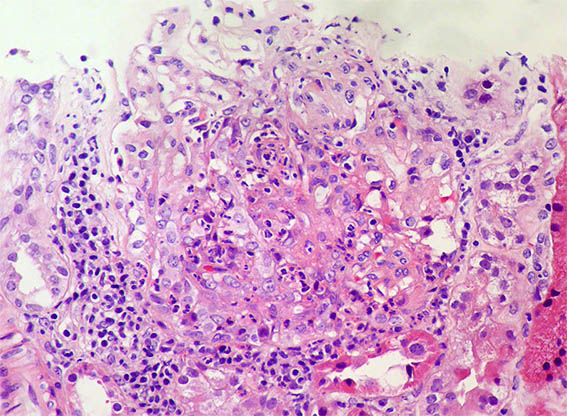

Figura 5. H&E, X400. Hipercelularidad endocapilar, exudativa, y una posible semiluna epitelial.